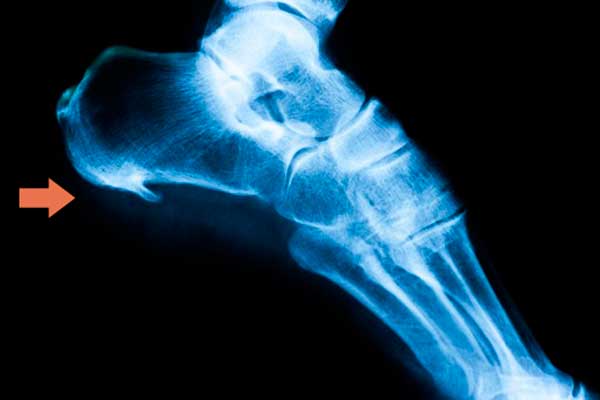

Es un crecimiento del hueso del talón en forma triangular o en punta de lanza, que se produce cuando la fascia plantar, que es un tejido fibroso que va del calcáneo hasta la base de los dedos, está sometida a un exceso de tracción y sobrecarga. Se produce una calcificación que provoca dolor agudo en el talón.